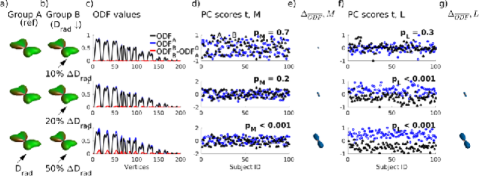

Figures 3 and 4 show results of the detection of differences between groups of 100 simulated ODFs of two crossing fibers. When comparing large differences (Fig. 3ab, bottom row, reduction of ), visual comparison of the average ODF-values (Fig. 3c) easily confirms the separation of PC-scores of both ODF-matrix (Fig. 3d) and Low-Rank matrix (Fig. 3f). When comparing smaller group differences however (Fig. 3, top two rows, and reduction of ), statistical testing of is not significant (Fig. 3d) ,while testing of , after separation of the individual variability in , does succeed in identifying the simulated group differences (Fig. 3f).

Figure 4 looks at the detectability of a broader range of changes of (Fig. 4a), (Fig. 4b) and crossing angle (Fig. 4c) between groups of simulated ODFs. Similarly, figure S1 studies the detectability of changes in number of fibers (Fig. S1a,b) and relative fiber weights (Fig. S1c). The left columns of Figure 4 and S1 plot the t-test test statistic and the right columns the t-test p-value. Changes in , and relative weight, which create more subtle differences in the ODF peaks, are better detected by analyzing the PC-scores of versus . Larger changes in the ODF, such as a shift in the ODF peak orientation by changing the crossing angle or adding fibers to the ODF, are detected equally well by both approaches. Note that there are almost linear relationships between the test statistics and the changes in diffusion parameters (Fig. 4, S1, left column).

The (Eq. 2) in Fig. 5 are a visual representation of the detected ODF group differences. They scale with the detected ODF group difference for simulated changes in (5a) and (5b) of one fiber bundle in a crossing pair and with changes of their crossing angle (5c). Both an increase in and a decrease in give rise to a larger peak, hence a positive (blue-colored) -lobe. A change in crossing angle gives rise to a positive (blue-colored) and a negative (red-colored) lobe scaling with the change in crossing angle (5c).